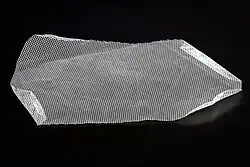

Verbreitet ist zudem die offene Implantation von Kunststoffnetzen, die aus resorbierbaren und nicht-resorbierbaren oder titanbeschichteten Komponenten bestehen können und meist in der Technik nach Lichtenstein des amerikanischen Chirurgen Irving L. Lichtenstein eingebracht werden.

Bei minimalinvasiven Techniken wird die Bruchpforte immer mit einem Netz verschlossen. Hier werden wiederum zwei Verfahren unterschieden:

Zum einen kann in der sogenannten TAPP-Technik das Netz laparoskopisch – das heißt über eine Bauchspiegelung vom Bauchraum aus – über der Bruchpforte platziert werden. Hierbei ist das Eingehen in die Bauchhöhle erforderlich, das Bauchfell muss aufgeschnitten und am Ende der Operation wieder verschlossen werden. Die Netzfixation erfolgt durch Metallclips, resorbierbare Clips, durch Annähen oder durch die Verwendung von Gewebekleber. Bei der TEP-Technik wird das Netz ebenfalls über minimalinvasive Zugänge nach einem vorsichtigen Auseinanderdrängen der Schichten der Bauchdecke über der Bruchpforte platziert.[22] Hierbei wird das Netz zwischen Bauchfell und Muskulatur ohne weitere Fixation eingelegt. Im Kindesalter wird bei den minimalinvasiven Verfahren kein Fremdmaterial (Netz) in die Leiste eingebracht, da dieses nicht mitwachsen kann. Es wird die über eine Bauchspiegelung sichtbare Bruchpforte mit einer Naht verschlossen.[23]

Die Verfahren, die die Bruchlücke mit einem Netz überdecken (sowohl offene als auch geschlossene), werden als „spannungsfreie“ Verfahren bezeichnet und sollen sofort belastbar sein und bei größeren Bruchpforten eine niedrigere Rezidivrate haben als die Methode nach Shouldice. Netzimplantate führen je nach Material (Kunststoff oder Titanisierte Oberflächen) zu unterschiedlichen gewünschten oder aber auch zu unerwünschten Vernarbungen, die wiederum Neuralgien (Nervenschmerzen) zur Folge haben können. Minimalinvasive Techniken werden zumeist in der frühen Erholungsphase von den Patienten als schmerzärmer empfunden und sind deshalb besonders bei beidseitiger Operation in einer Sitzung indiziert. In der Spätphase werden jedoch gelegentlich schwer behandelbare Schmerzzustände beobachtet, die möglicherweise auf Metallclips zurückzuführen sind, mit denen das Netz vor allem bei der TAPP-Technik gegen Verrutschen fixiert wird. Bei der TEP-Technik kommen keine Metallclips zur Anwendung. Bei der TAPP-Technik werden Metallclips angewandt, aber auch resorbierbare Clips oder Fibrinkleber, um Nervenschädigungen zu vermeiden. Bei den modernen Netzimplantaten, die mit einer sehr dünnen Schicht von Titan beschichtet sind, kommt es zu einer hydrophilen Verbindung mit dem Gewebe, so dass meistens auf die problematische Fixierung verzichtet werden kann. Bei der TEP-Technik ist – im Gegensatz zur TAPP-Technik – ein operatives Eingehen in die Bauchhöhle mit Aufschneiden und Wiedervernähen des Bauchfells nicht erforderlich, da die minimalinvasive Operation lediglich zwischen den Bauchdeckenschichten erfolgt. Eine Verletzungsgefahr für die inneren Bauchorgane ist bei der TEP-Technik daher ausgeschlossen. Bei der TAPP-Technik sind hier gelegentlich Fälle beschrieben. Insbesondere bei Voroperationen in der Bauchhöhle mit den entsprechenden Verwachsungen ist das Verletzungsrisiko bei der TAPP-Technik deutlich erhöht. Eine weitere gute Indikation zur Anwendung minimalinvasiver Techniken ist die Operation von Rezidivhernien, das heißt von Leistenbrüchen, die früher schon einmal offen operiert worden waren, jetzt jedoch wieder aufgetreten sind.